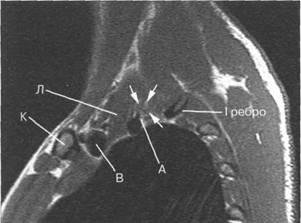

лизации

плечевого

сплетения и

его ветвей. С

помощью

современных

томографов и

программного

обеспечения

удается

получить

ин 10510f510k формацию

не только об

окружающих

плечевое сплетение

тканях, но и о

самих

нервных

структурах.

I располагается позади. Иногда удается хорошо различить ин 10510f510k дивидуальное деление пучков. Ла-